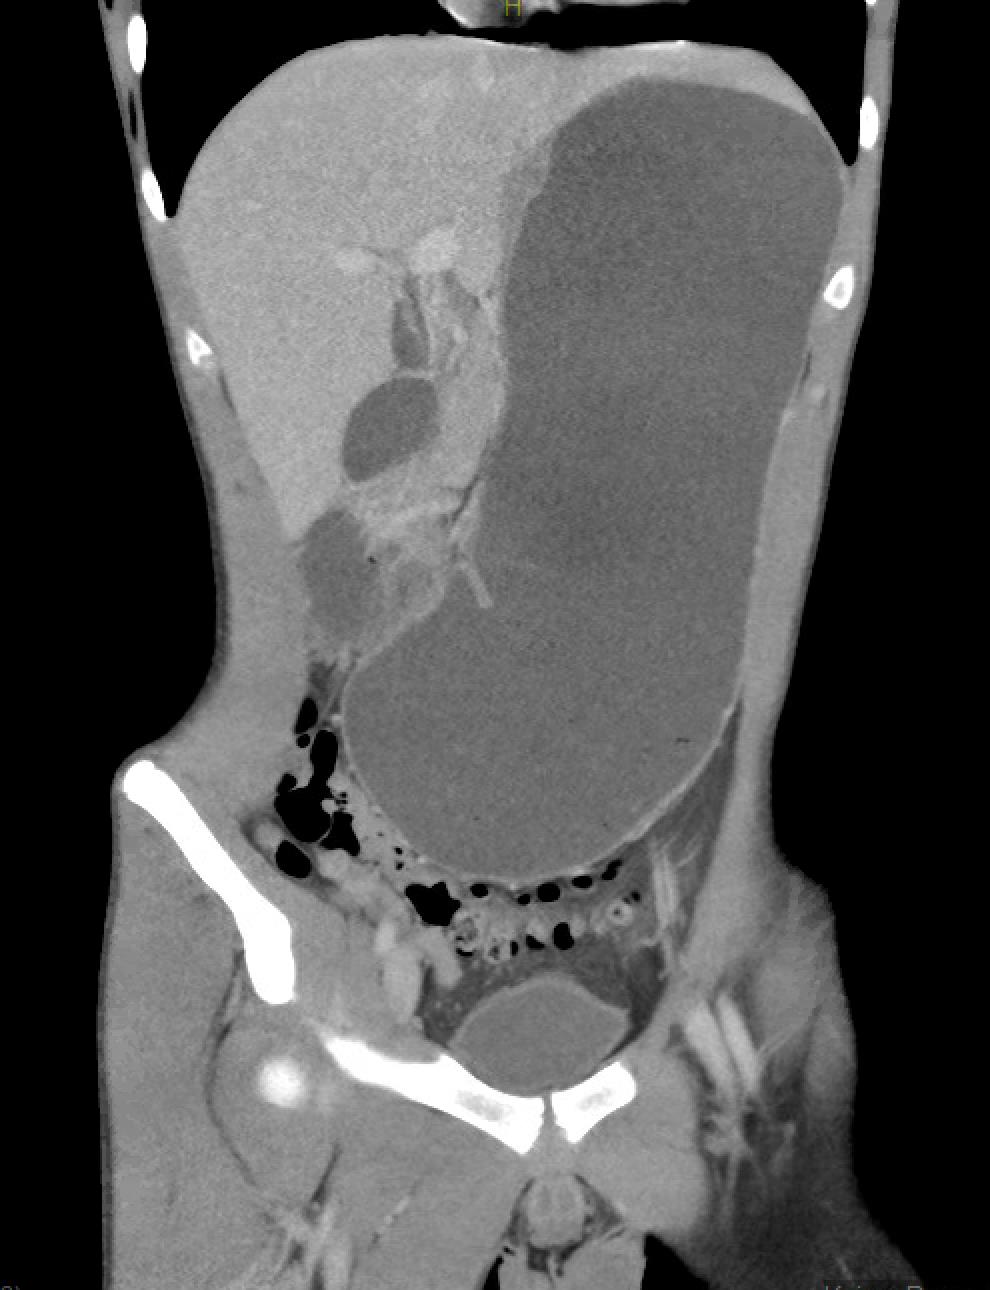

Abdominal computed tomography angiography during hospitalization

FINDINGS (abbreviated): Normal robust enhancement of abdominal aorta, origins of celiac, superior mesenteric and renal arteries are demonstrated. The aortomesenteric angle measures 14 degrees. The aortomesenteric distance at the level of the duodenal crossing is 6 mm.

IMPRESSION:

- Interval resolution of previously demonstrated marked distention of the stomach. Proximal duodenum is mildly dilated, but significantly improved compared to prior.

- Both the aortomesenteric angle and aortomesenteric distance are decreased, as may be seen with SMA syndrome. Clinical correlation and follow-up care are recommended.

- Left chest tube is present with small left pneumothorax.

- Subcutaneous air is present with soft tissues in the lower chest.

- Small amount of posterior pneumomediastinum is present.

- Mild splenomegaly is present. The spleen appears elongated and relatively thin transversely.